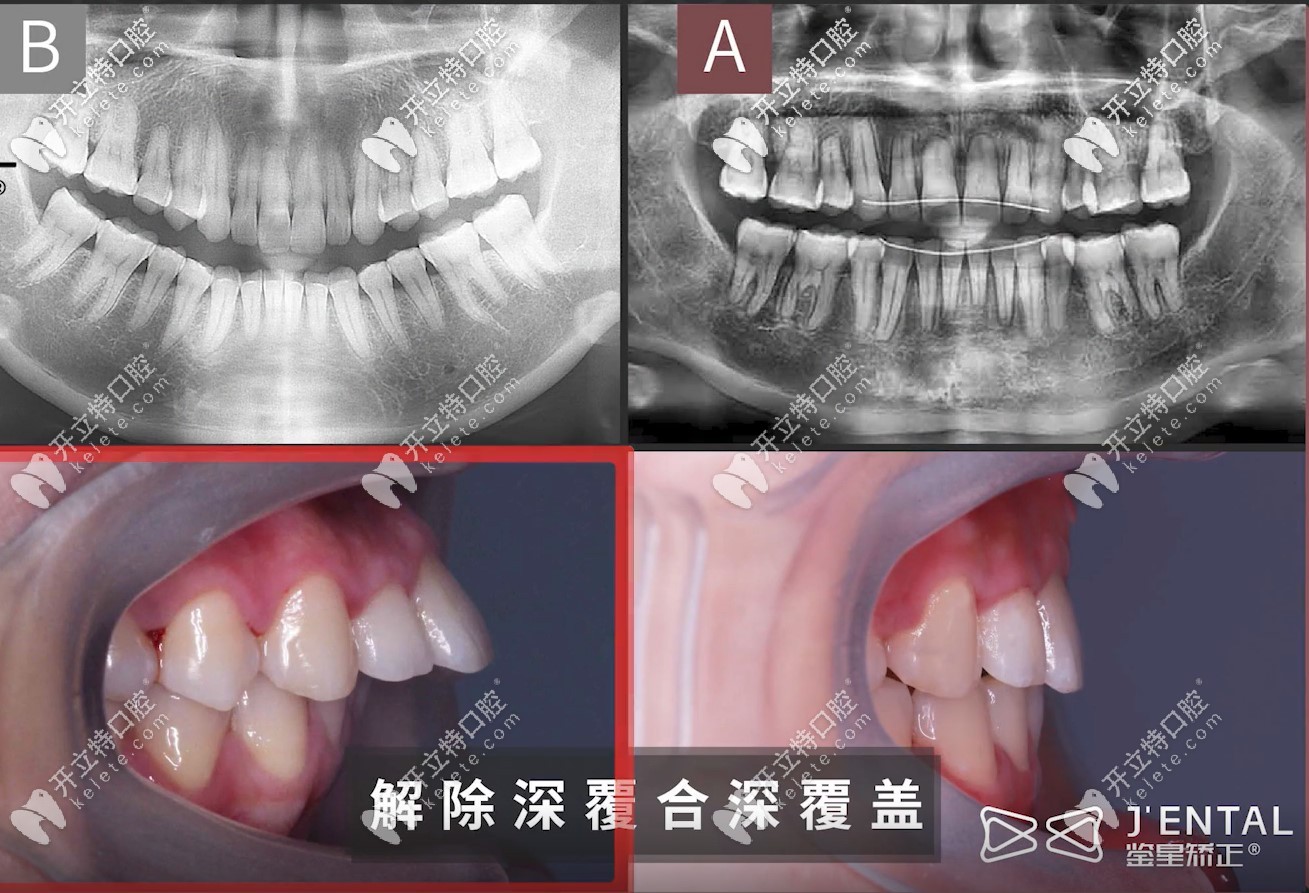

骨性深覆蓋+深覆合的小姐姐,外加露齦笑,矯正難度是非常大,在矯正過(guò)程中,為了內(nèi)收前牙,醫(yī)生打了很多的骨釘,耗費(fèi)3年時(shí)間,不僅解決了10個(gè)毫米的露齦笑問(wèn)題,牙齒還內(nèi)收了7mm左右哦!

從這張圖,可以明顯看出,牙齒內(nèi)收的尺度相對(duì)比來(lái)說(shuō)還是比較大滴↓↓↓

牙齒內(nèi)收7mm,順便解決了10mm的露齦笑